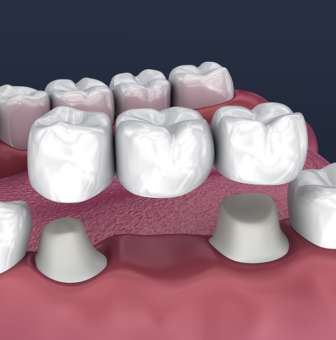

Crowns & bridges

Crowns and bridges are fixed dental restorations used to strengthen damaged teeth or replace missing ones. A crown covers and protects a weakened tooth, while a bridge fills the gap of one or more missing teeth by anchoring to the surrounding teeth. They improve chewing, speaking, and restore a natural-looking smile.

- Dental Crown : A protective cap placed over a weak or damaged tooth.

- Dental Bridge : A fixed solution to replace one or more missing teeth.